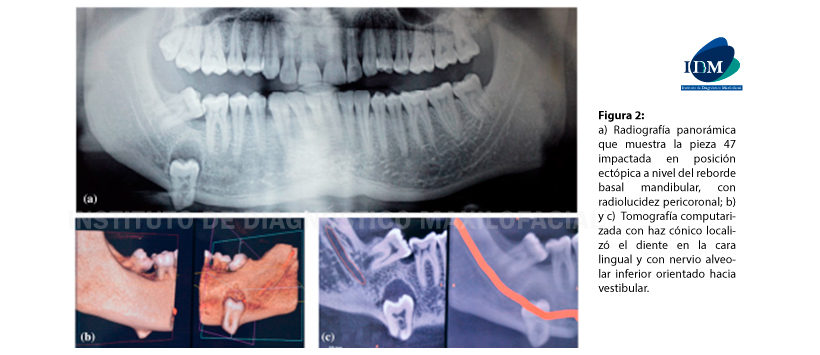

Figura 2: a) Radiografía panorámica que muestra la pieza 47 impactada en posición ectópica a nivel del reborde basal mandibular, con radiolucidez pericoronal; b) y c) Tomografía computarizada con haz cónico localizó el diente en la cara lingual y con nervio alveolar inferior orientado hacia vestibular.